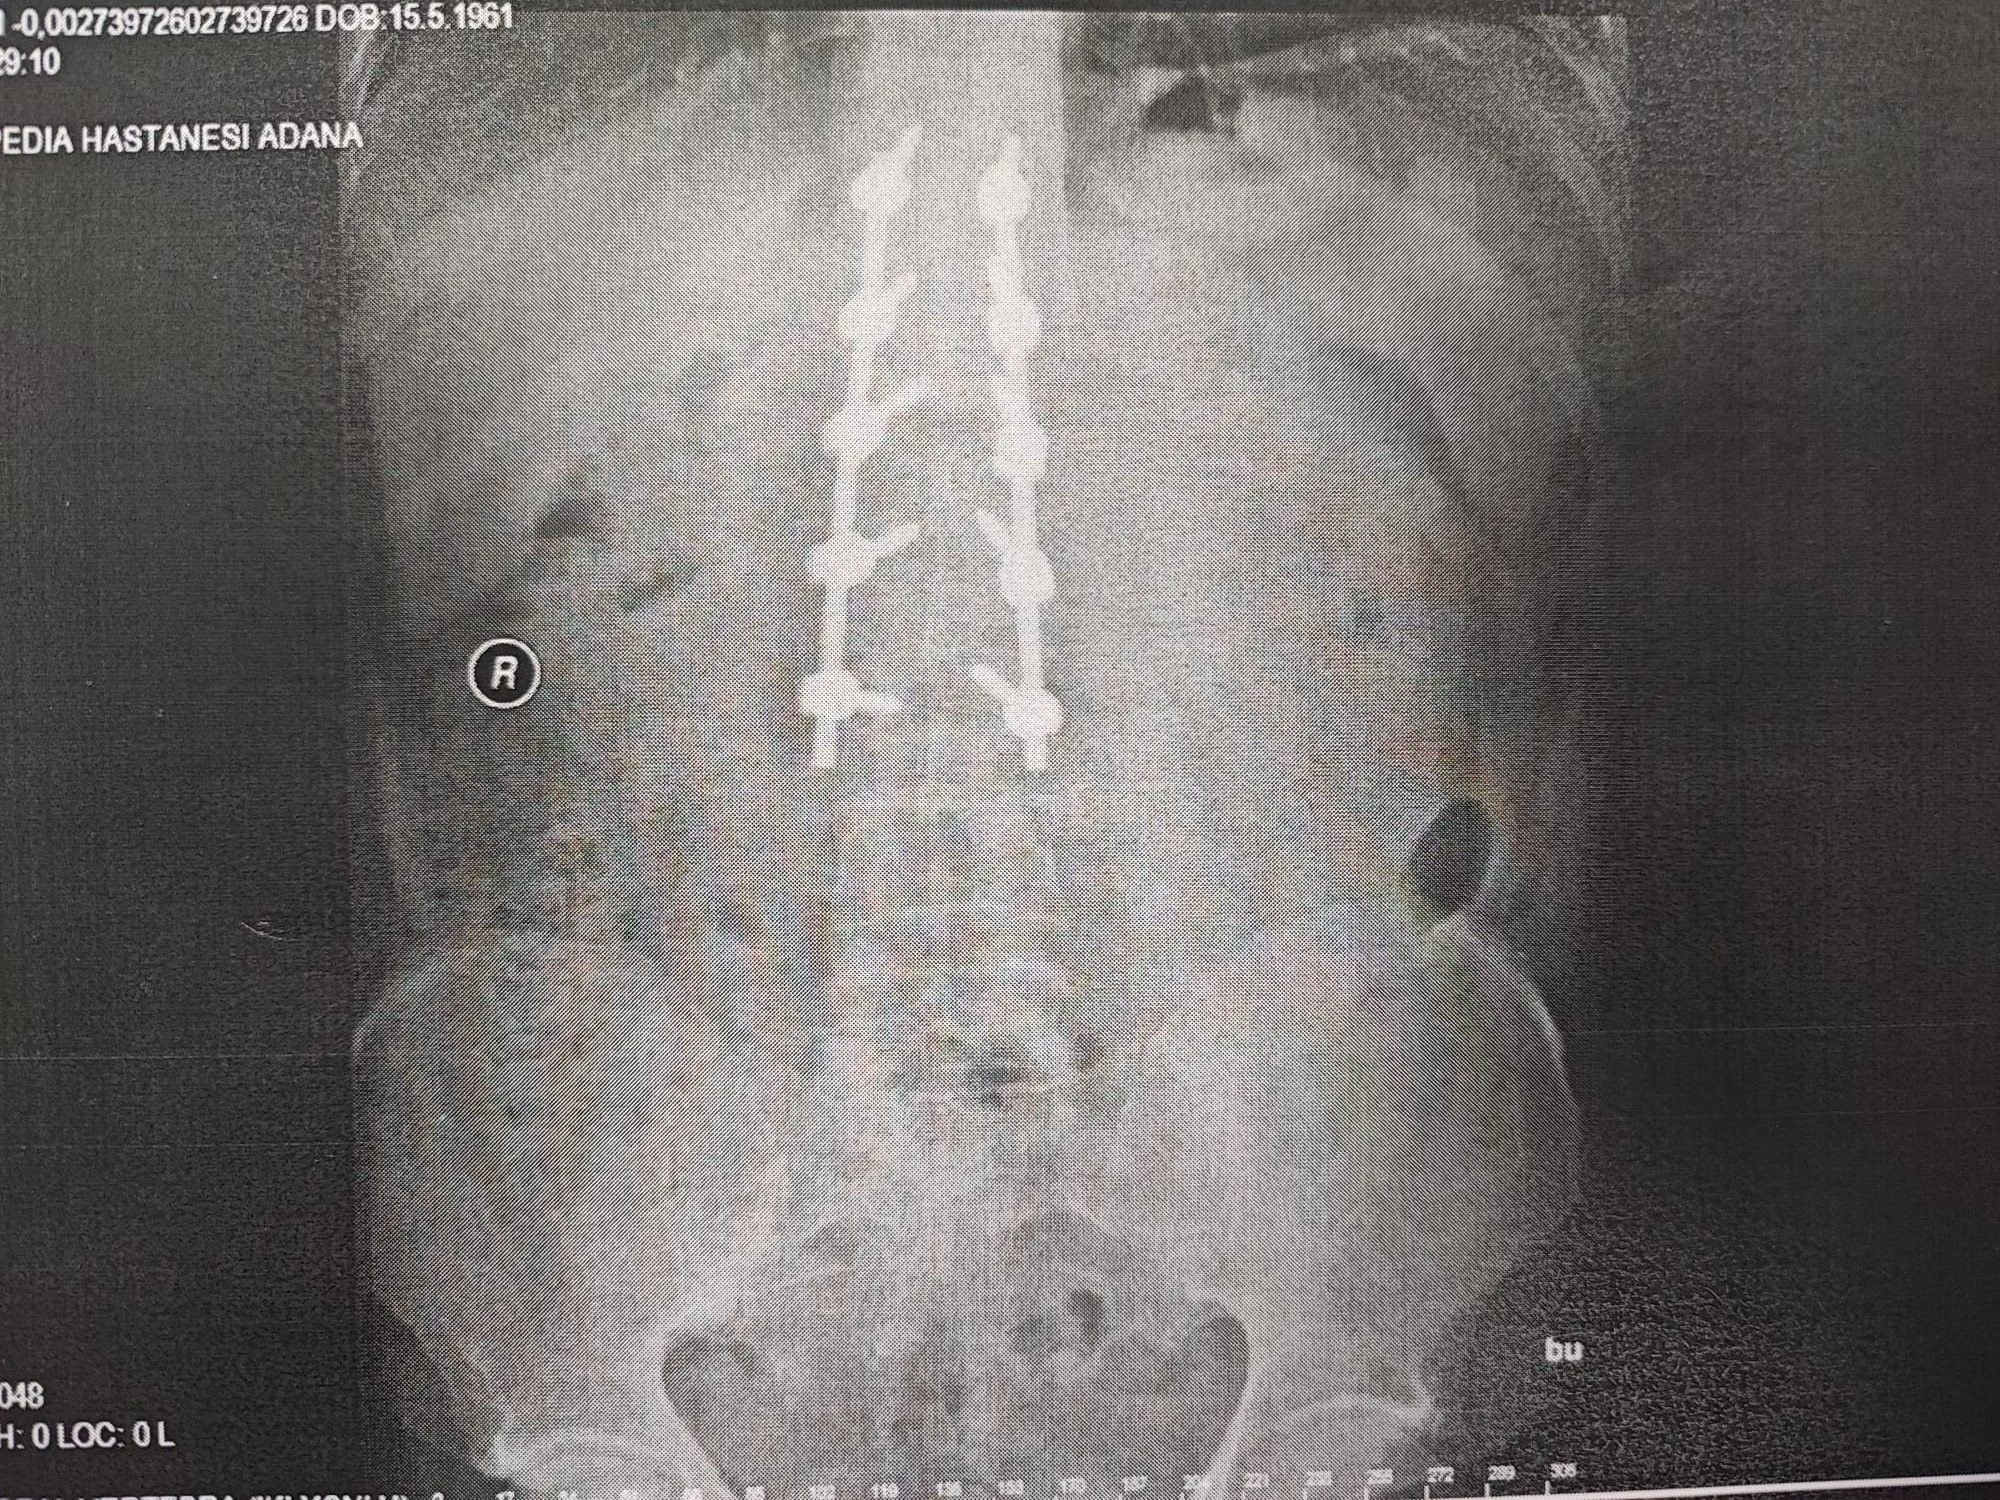

Omurga kemiği kırıldığı tespit edilen Aras’a 10 platin takıldı. 3 ay süren tedavi sonrası Aras, ayağa kalkabildi. Bu arada otomobil kaza sonrası tamir edilmek üzere bayiye götürüldü. Aras, iyileştikten sonra aracını almaya gitti ancak takılan farda bir gariplik olduğunu fark edip araştırma yaptığında orijinal olmadığını çıkma parça takıldığını ve takıldı denilen 11 parçanın da takılmadığını tespit etti.

Aras, teknik hata yüzünden ölümden döndüğünü 10 platin ile yaşamak zorunda kaldığını belirterek, “Ortalama 3 ay boyunca tedavi sürecim devam etti. Omurga kemiğim kırıldı ve şuan hala 6 buçuk santim boyunda 10 tane çelik platin var. Dik durabilmem için çelik vidalar var. Ancak onların sayesinde ayakta durabiliyorum. 2019 yılında meydana geldi kaza ve bana araba artı para teklif ettiler. Bende, aynı arabanın birebir aynısı ya da bir üst modeliyle değiştirilmesini istedim. İlk önce bir alt modelini vermeyi teklif ettiler. Üstüne de para verelim dediler. Ben bunları kabul etmedim, zararımın giderilmesini istiyorum. Bayiyi hurda parça takmaktan dolayı şikayet ettim. Arabayı imal eden Mercedes’i de dava ettim” diye konuştu.